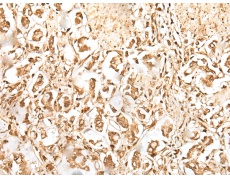

IHC positive control: |

Human esophagus cancer and Human lung cancer |

IHC Recommend dilution: |

25-100 |